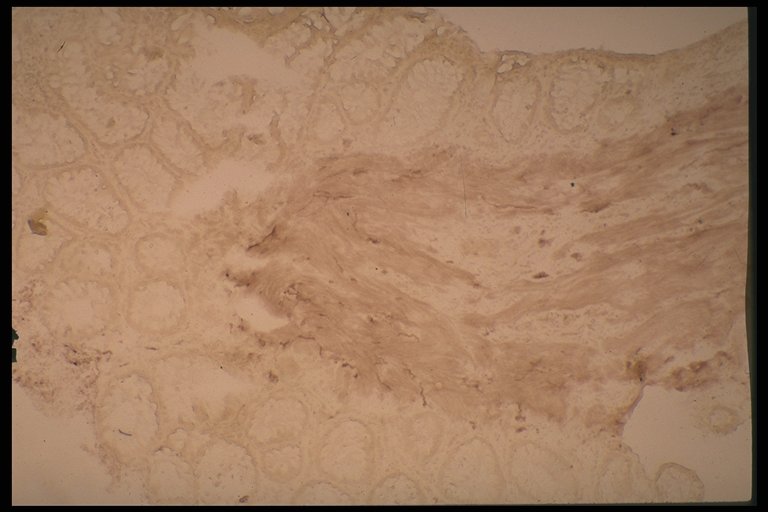

Normal acetylcholinesterase activity in normal specimen